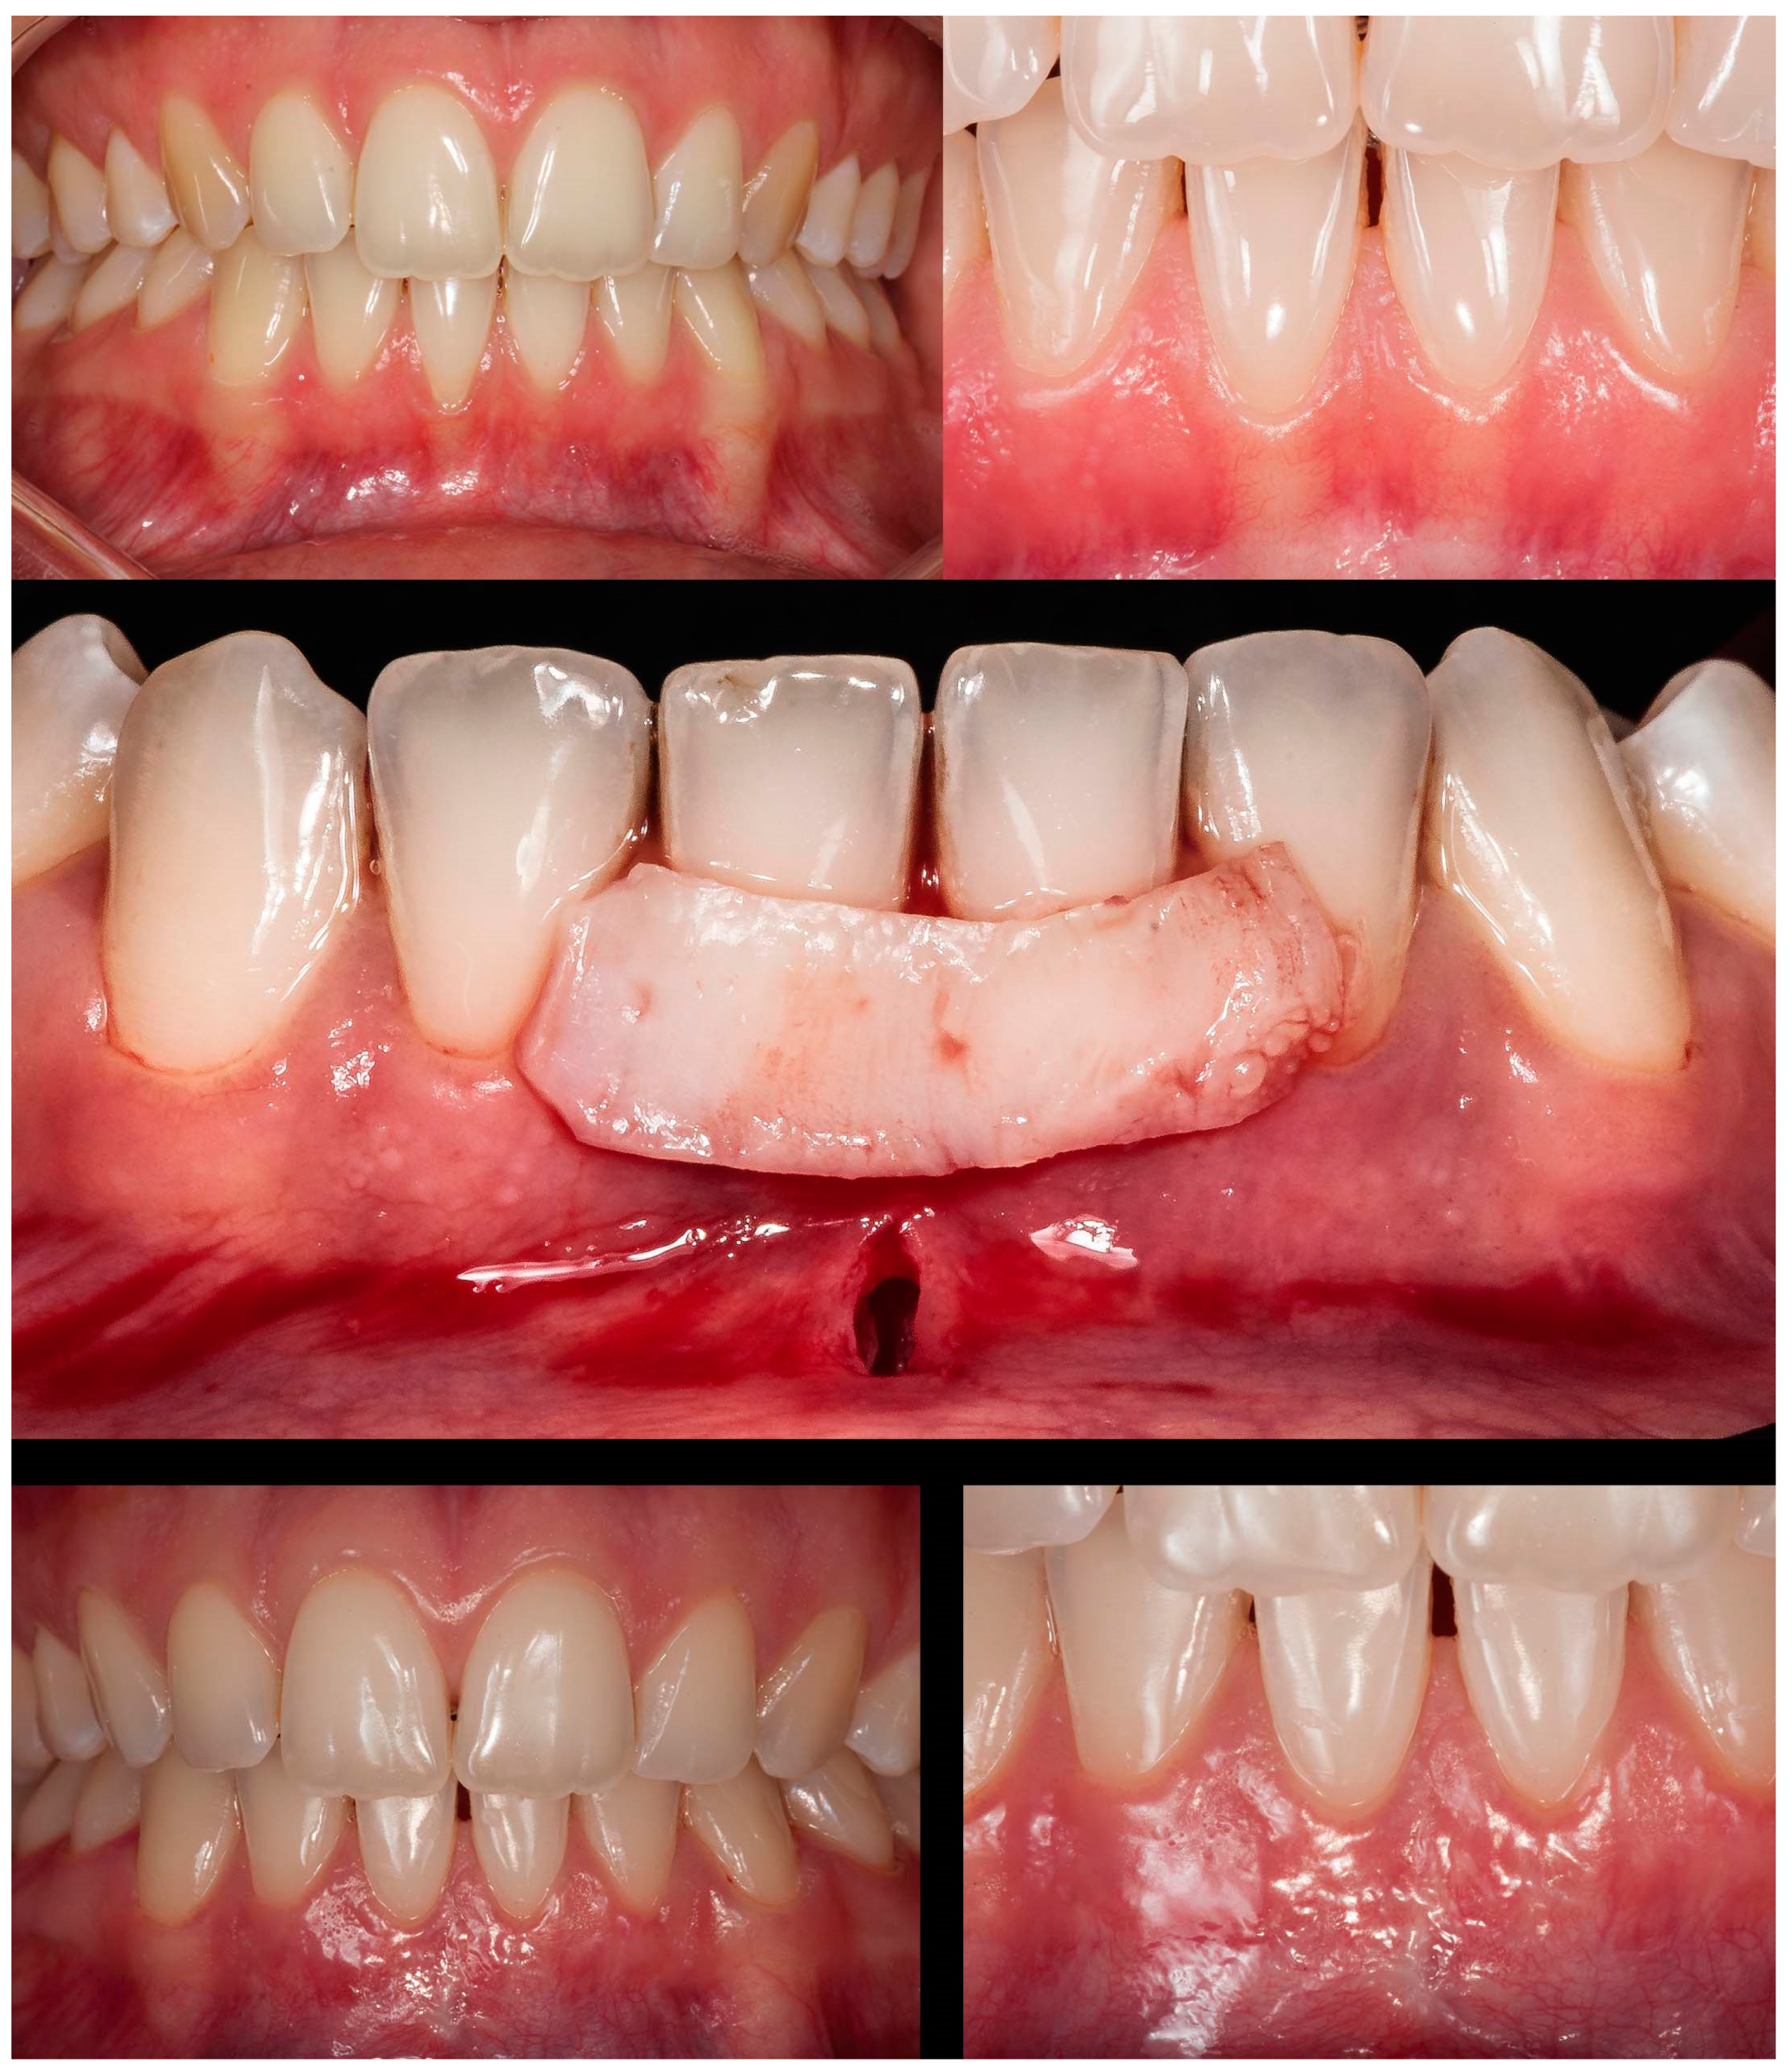

The seventh case (

Figure 8) differed from the rest because it involved an esthetic area in an anterior maxillary region. Even with a gingival RT1 in teeth #12-#22, respectively, with 1mm, 1.5mm, 2mm, and 1.5mm, teeth #11 and #21 presented a wide GR (3mm and 4mm, respectively). The case was conducted without adverse events using two linear vertical incisions on the distal to the central incisors. A buccal suture in the facial region of the teeth was made using composite. An adequate healing process was found after 7 days and 1 year, which was permitted by the tissue stability achieved in soft tissue management. The success rate was 100% for RC.

The 8

th case was a RT2 (

Figure 9), with interproximal attachment loss, involving #32 to #42 (GR of 2mm, 3mm, 3mm, and 1mm, respectively). After explaining that the success rate is reduced in these cases compared to RT1, the patient accepted it and was surgically treated. Before starting the procedure, composites were placed in the interproximal of the teeth to apply the double-crossed suture posteriorly [

14]. De-epithelized CTG was collected from the hard palate, and two distal vertical linear incisions were made. The mixed tunnel was performed, and the graft was inserted through the tunnel. The suture was coronally positioned. After 1 year, the healing was favorable, with 100%, 82.35%, 81.25%, and 58.34%, respectively, success rates reached.

Figure 8.

Case 7 shows initial pictures of the GR defects (#12-#22); a picture showing the final aspect immediately after surgery; and the healing period after 14 days and 1 year.

Figure 9.

Case 8 shows initial pictures of the multiple GR defects (#42-#32) and thin phenotype present; CTG over the receptor site and two vertical incisions at the distal to apply MiTT; a picture showing the final aspect immediately after surgery; and the healing period after 1 month.